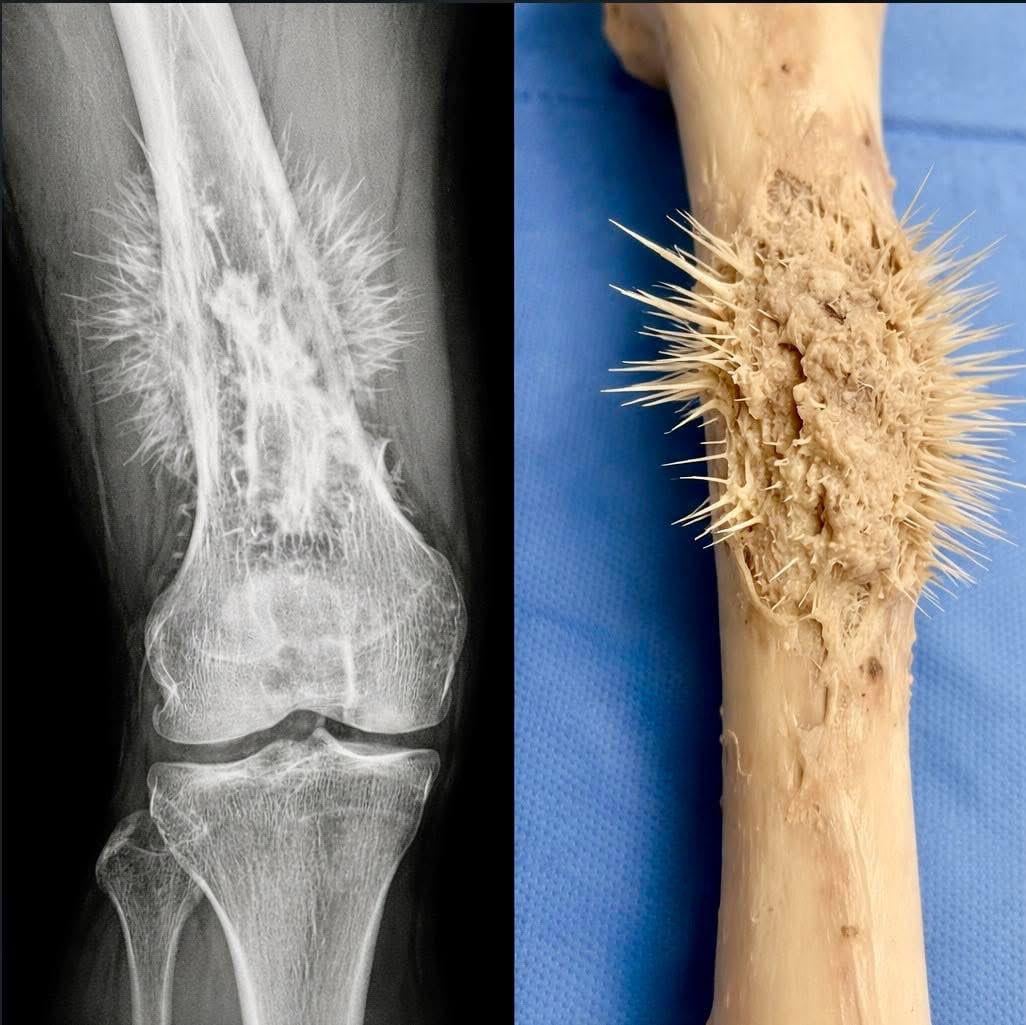

Don’t know whether to be amazed or terrified.

That looks painful as fuck.

Those bone spikes look painful

Just imagine like itching your knee. Breaking off a bunch of those lil spikes into your knee and there just floating around in there. wtf that sounds like hell.

Do we know of any particular reason they tend to grow fucking *spikes*?

I wish I had the grades for med school man, everyones reaction is to be shocked and horrified, and I am too, but mostly I’m just FASCINATED. How does it do that? Why does it form like a pincushion? Why are there so many types of cancer in general?? It seems like research in the field of oncology is never done, just because cancer forms in so many different ways. Id love to help.

I lost a lovely old greyhound girl to this cancer it came on fast. It is common in greyhounds apparently. But wow – what a terrible thing when the body does this to us. I don’tknow how they flensed this bone to show the cancer whether the person died or lost their leg becaus eof it, but yes this is really interesting but also once seen not unseen and I hope I never have to contend with it again irl now I have seen it. (Our darling old girl a week before diagnoses and euth.)